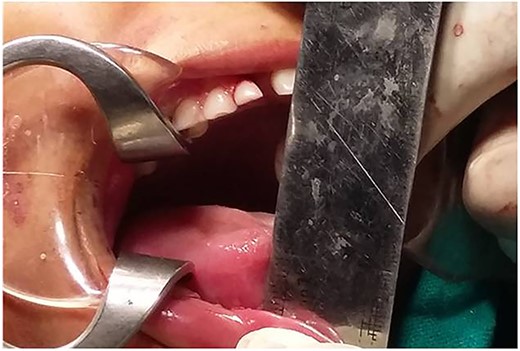

The clinical examination revealed a hypoplastic mandible with lower facial asymmetry and fullness of cheek on right side. The patient had trismus with a maximal incisal opening (MIO) of 5 mm. There was no palpable movement over the right TMJ and only slight rotation on left side (Figs 1 and 2).

Mouth opening of ~37 mm was done using Hister’s jaw opener at time of surgery (Figs 9 and 10). Suction drain was placed, and the flap was sutured using 3–0 vicryl for deeper layers and skin was closed using 4–0 prolene.